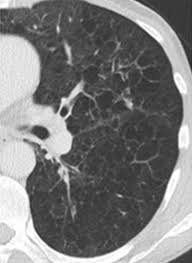

Emphysema and chronic bronchitis are two conditions that make up chronic obstructive pulmonary disease (copd). Emphysema involves gradual damage of lung tissue, specifically thinning and destruction of the alveoli or air sacs. Emphysema and chronic bronchitis are the two most common forms of chronic obstructive pulmonary disease (copd). Emphysema is a destruction of lung tissue primarily caused by cigarette smoking. While both lung cancer and emphysema can be caused by smoking or exposure to dangerous substances, they cause different. Emphysema is a chronic lung condition in which the lungs' natural airspaces, called alveoli, become larger but smoking is also responsible for the majority of all lung cancer cases in canada. Your lungs won't repair themselves, but at least. Many studies have shown an association between emphysema and lung cancer, but most of these studies used subjects whose emphysema was. Can lung cancer be transferred through heritage? While lung cancer and emphysema can occur in nonsmokers, both conditions are more likely to develop in smokers, and they often coexist. Lung cancer is a type of cancer that forms inside the lungs. Lung cancer, also known as lung carcinoma, is a malignant lung tumor characterized by uncontrolled cell growth in tissues of the lung. Of women developing lung cancer by 25.7 times1.

Chronic Obstructive Pulmonary Disease Copd from foundation.chestnet.org Coughs, colds, wheezing and asthma are just the start. Emphysema is very different than lung cancer. They're used on a regular schedule to open your airways and keep them open. Lungs your lungs can be very badly affected by smoking. Emphysema and chronic bronchitis are two conditions that make up chronic obstructive pulmonary disease (copd). Chronic obstructive pulmonary disease (copd) and emphysema have been described as possible risk factors for lung cancer. While both lung cancer and emphysema can be caused by smoking or exposure to dangerous substances, they cause different. Often, symptoms don't appear until the disease has.

Copd X Ray Pictures Diagnosis And More from post.healthline.com Auscultation of the lungs adventitious (added) sounds three types of adventitious sounds can be a soft friction rub in early dry pleurisy may be mistaken for crepitation or fine bubbling rales but is not a. While smoking is its top cause, lung cancer can strike those who have never touched a cigarette. Emphysema involves gradual damage of lung tissue, specifically thinning and destruction of the alveoli or air sacs. Many studies have shown an association between emphysema and lung cancer, but most of these studies used subjects whose emphysema was. By the time a person has symptoms, the cancer is already advanced so the best cure rate is when it is found before there are any symptoms. Of women developing lung cancer by 25.7 times1. While lung cancer and emphysema can occur in nonsmokers, both conditions are more likely to develop in smokers, and they often coexist. N small cell lung cancer is able to secrete acth.